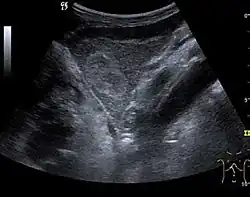

The ultrasound appearance is a well defined lesion, with very thin, almost unapparent walls, without circulatory signal at Doppler or CEUS investigation. The content is transonic suggesting fluid composition. The presence of membranes, abundant sediment or cysts inside is suggestive for parasitic, hydatid nature. Posterior from the lesion the acoustic enhancement phenomenon is seen, which strengthens the suspicion of fluid mass. They typically displace normal liver vessels but no vascular or biliary invasion occurs.

-

Liver cyst -